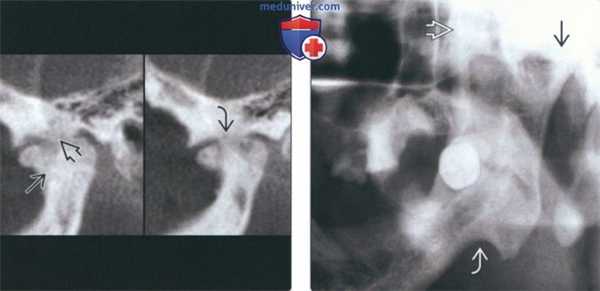

(Слева) На корональной КТ без КУ у этого же пациента определяется выраженное увеличение правого мыщелка, соединенного с височной костью костным мостиком с наружной стороны. Суставное пространство облитерировано. Шейка мыщелка и ветвь нижней челюсти утолщены.

(Справа) На аксиальной КТ без КУ у этого же пациента определяется склероз и увеличение всех размеров мыщелка со слиянием с височной костью. Суставное пространство не визуализируется.